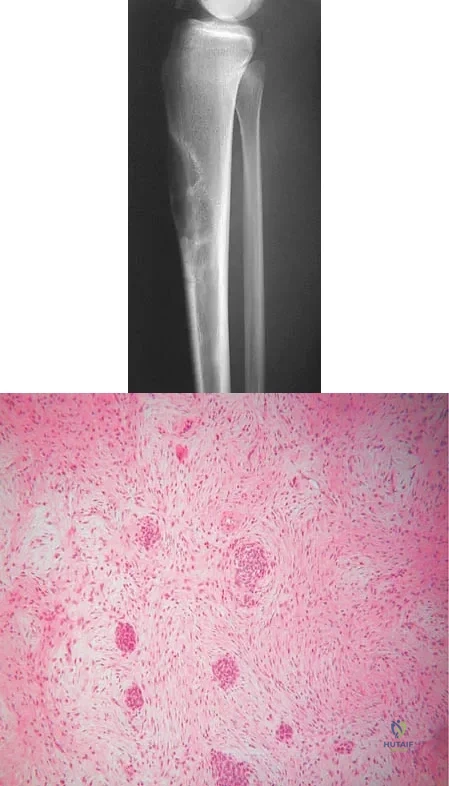

Question 14

Figures 19a and 19b show the AP and lateral radiographs of an 18-year-old man who has had knee pain for 3 months. Figure 19c shows a histopathologic photomicrograph of the biopsy specimen. Which of the following factors is most likely to affect his survival?

Explanation